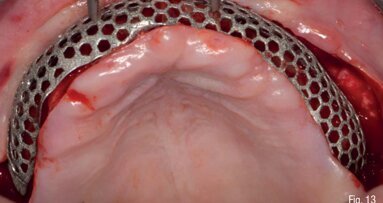

La Rigenerazione Ossea Guidata (GBR) è una delle tecniche più utilizzate e descritte in letteratura per la ricostruzione dei difetti ossei, per ottenere ...